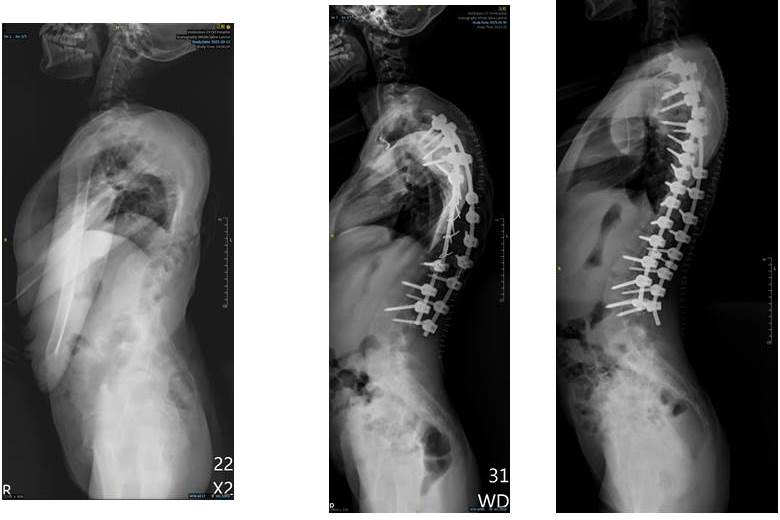

回台後他與院方討論,立刻獲得院方的全力支持,除了與嘉基脊椎微創中心主任黃儀鴻醫師合作,另外也請到台北慈濟的骨科權威曾效祖醫師參與手術。考量到誠心的神經與血管長年受壓迫,不適合一次變動太多以免造成癱瘓風險,因此分別於今年10月20日、11月3日各進行一次手術,兩次手術時間合計超過30個小時,成功讓側彎角度來到57度,從外觀上來看,誠心的背部已打直,心肺也不再受壓迫,身高更從135公分「長高」到150公分,接下來她還需要長期的復健,訓練呼吸與恢復重心。

嘉基院長姚維仁表示,醫院的「人道與海外關懷基金」善款由社會大眾捐獻,多用在海外義診以及弱勢者的國際醫療需求。在台灣由於有健保,醫療可近性也高,大部分的脊椎側彎患者會能及時就醫,先透過背架或其他方式矯正治療;但若持續惡化到了40度,便會歸類為重度脊椎側彎,建議進行手術。誠心小妹妹因為受限於經濟因素、當地醫療與政治現況,無奈之下才使側彎發展到驚人的160度。現在台灣已鮮少有如此嚴重的脊椎側彎個案,這次手術是由多位有經驗的醫師共同執刀,並憑藉嘉基智慧手術大樓最先進高端設備,以最新的脊椎固定骨釘以及高階術中影像系統、術中導航、神經監測等,帶著各界的支持一起讓誠心的生命成功轉彎,也祝福她有幸福健康的未來。